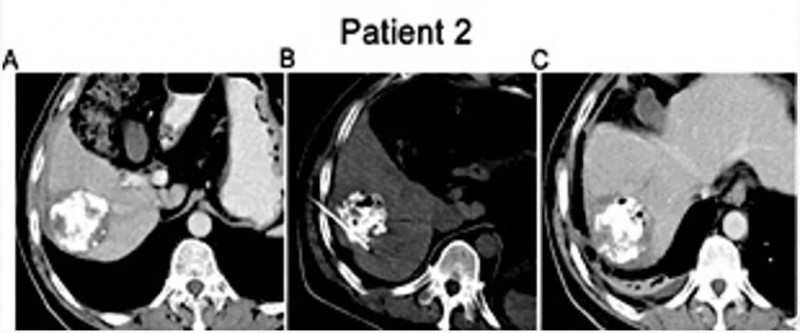

值得一提的是,A组2例典型患者,在治疗后均达到部分缓解(PR)。

患者1:是一位68岁女性,患IVA期非小细胞肺癌(NSCLC),治疗前左肺下叶可见3.8×1.8×2.4cm片状肿瘤;治疗90天后CT显示肿瘤缩小至2.5×1.2×2.1cm(详见下图)。

▲图源“JCI”,版权归原作者所有,如无意中侵犯了知识产权,请联系我们删除

患者2:是一位57岁男性,患IVA期非小细胞肺癌(NSCLC),治疗前左肺下叶存在6.6×5.5×6.2cm肿块;治疗90天后肿瘤缩小至6.1×4.1×4.8cm(红色箭头示肿瘤位置)。